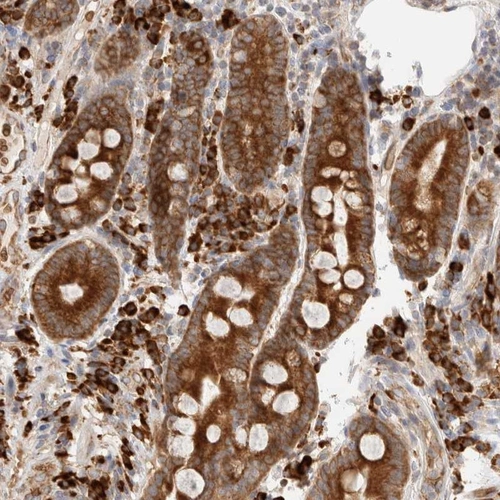

Immunohistochemical staining of human duodenum shows strong cytoplasmic positivity in glandular cells and a subset of inflammatory cells.